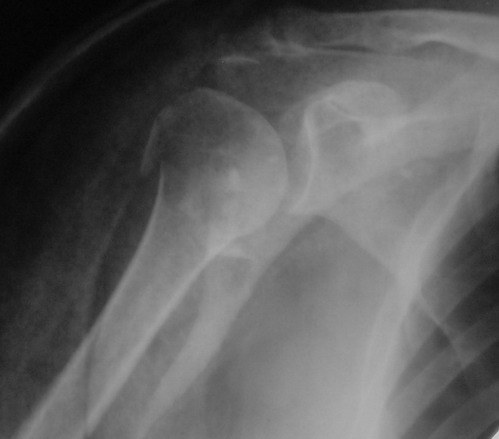

Снимки на 1-е сутки после репозиции и на 8- сутки после репозиции.